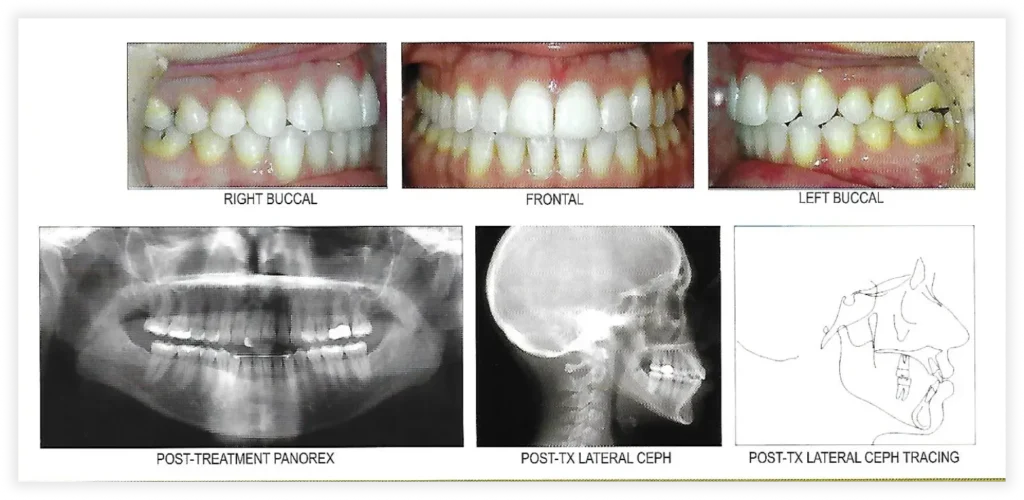

Smile Gallery

Take a look at some of our cases and successful transformations below.

Case #2

Initial Photos

Final Photos